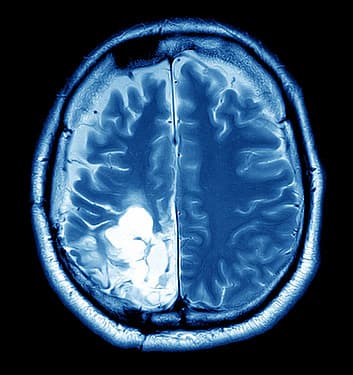

Brain Tumor Detection

Medical professionals require high-accuracy automated tools to assist in analyzing MRI images for tumors.